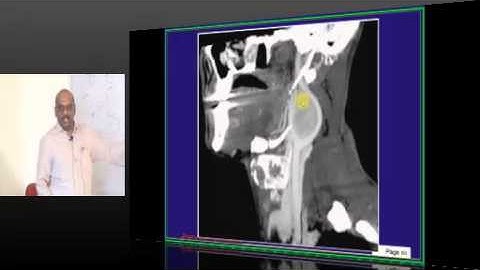

NEETPG Image based MCQ Mock Test Discussion 1503 Lec 01